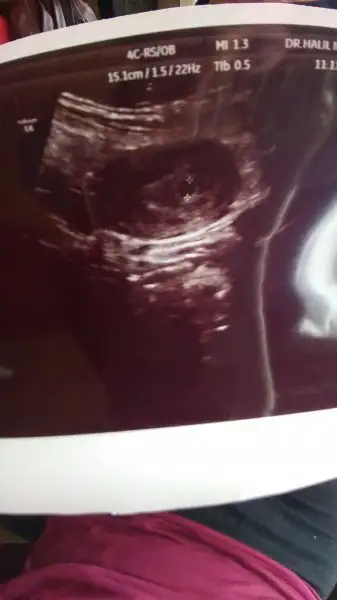

Canım benim çok sevindim. Artık sıra kalp atışındaKızlar günaydınnnn şimdi çıltım hastaneden keseyi gördük çok şükür bebeğim 4 haftalıkmış 2 hafta geriden gidiyoruz geç döllenme varmış![]()

Ayy bende keseyi gördüğüm halde hala heycanlıyım canım seni çok iyi anlıyorum o kadar hoş bir duygu ki ya buda bebişimin kesesi teyzesiiiiiİnşallah canım çok sabırsızlanıyorum

Ayy bende keseyi gördüğüm halde hala heycanlıyım canım seni çok iyi anlıyorum o kadar hoş bir duygu ki ya buda bebişimin kesesi teyzesiiiii![]()